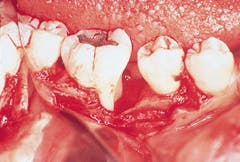

Surgical exposure of her mandibular right first molar can be seen in figure 3. Note that the lesion is limited to the mesial aspect of the first molar. The bone height is completely intact on the distal aspect of the second bicuspid. The type of intrabony defect present in this photograph is known as a three-wall defect, and it is very amenable to bone-grafting procedures.

Granulation tissue had been removed from the intrabony lesion prior to taking the photograph. However, no root planning had been performed. Note that mineralized accretions are not evident on the mesial aspect of the mandibular molar adjacent to the bony defect.

Calculus is not typically observed on the root surfaces adjacent to the bone defects associated with localized juvenile periodontitis. This is in contrast with the deep intrabony defects that can occur in patients with adult periodontitis. Minerals that compose the calculus do not cause bone loss, but the accretions have rough surfaces which are bacterial or plaque retentive.

Figure 3: Surgical exposure of the bony defect on the mesial aspect of tooth #30.